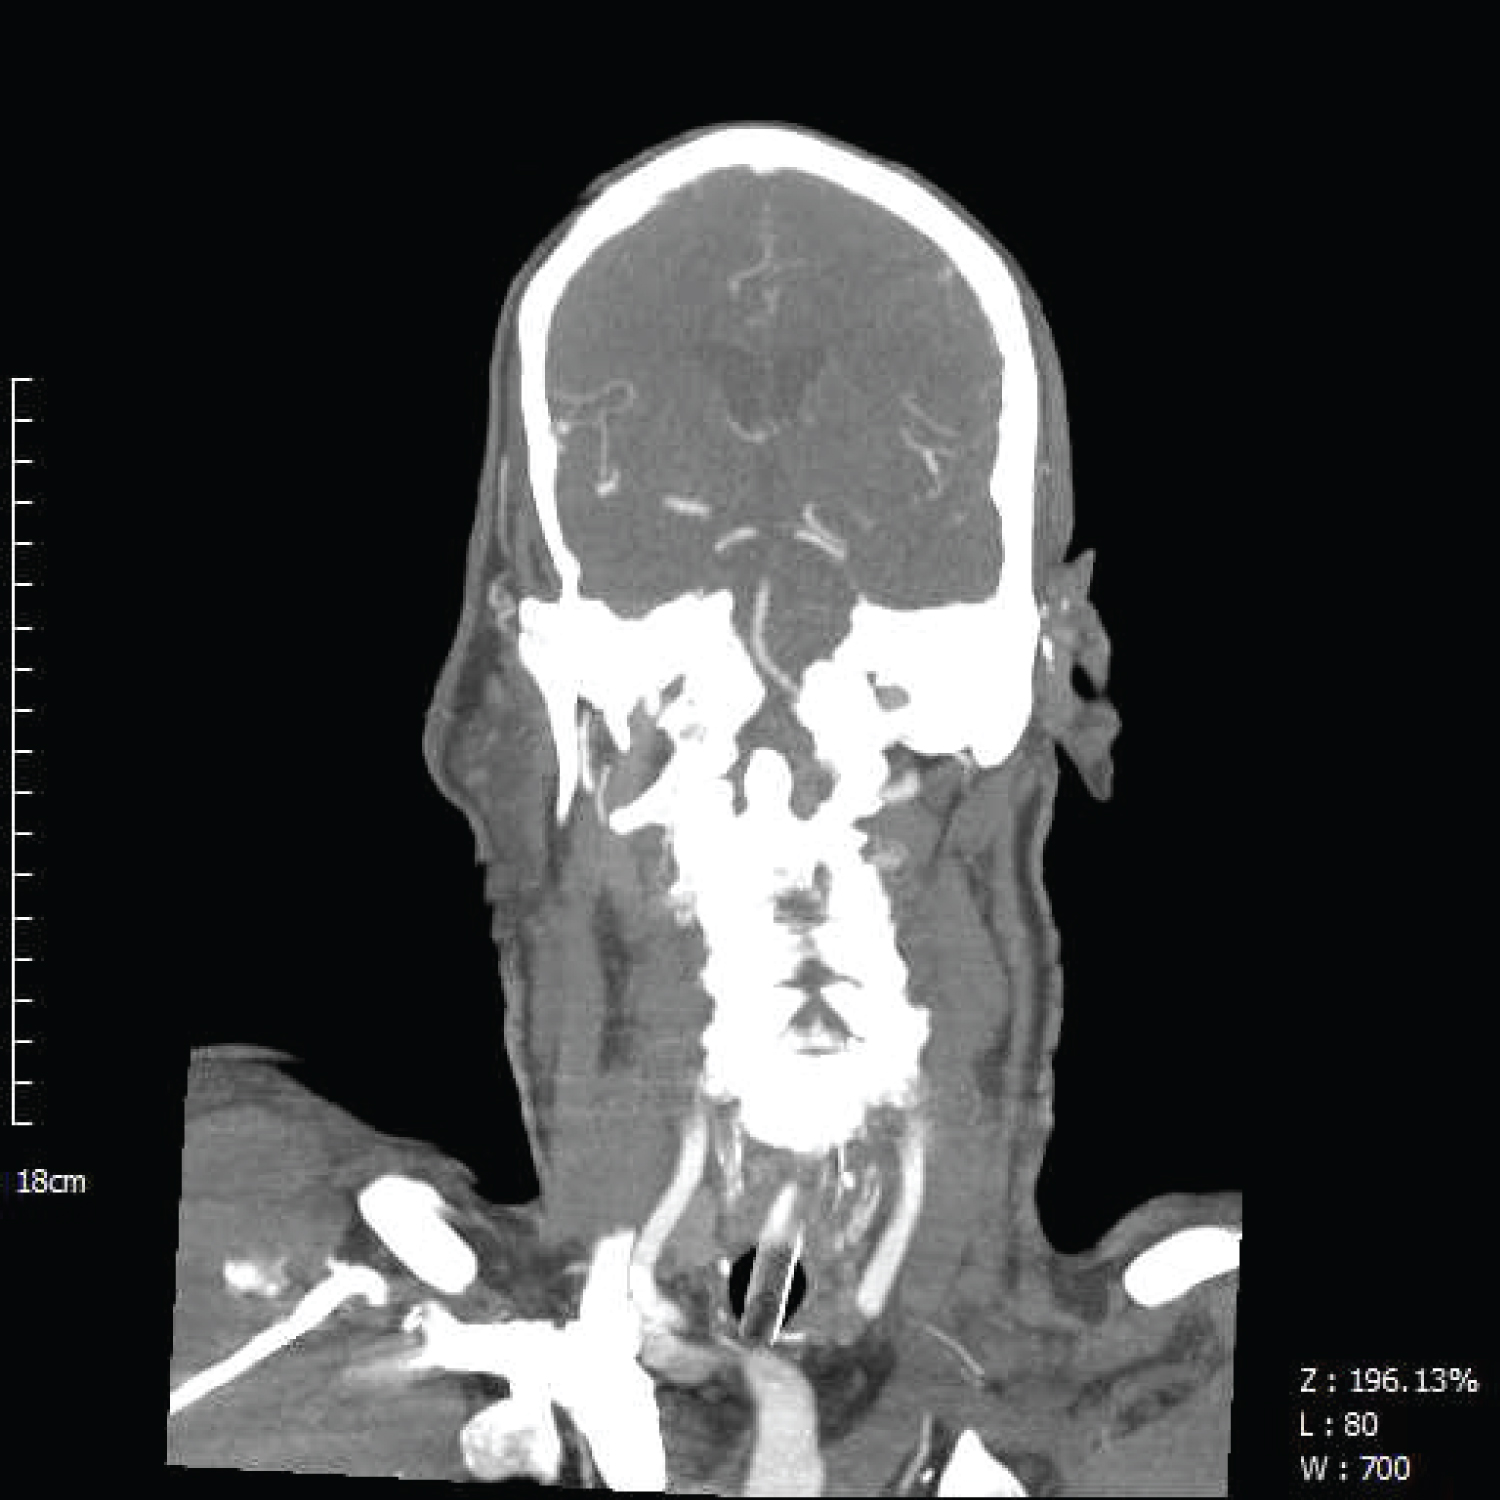

Figure 3: Arrow indicates contrast ceasing in basilar artery in coronal view.

To confirm basilar artery occlusion (BAO), he underwent brain and neck CT angiography (Figure 2 and Figure 3) and brain MRI (Figure 4). He admitted for endovascular basilar artery thrombectomy and had an uneventful follow up after 2 months.

BAO is a rare condition, more common in elderly population and usually caused by atherosclerosis or cardiac emboli [1]. The basilar artery supplies the pons and the midbrain. Depending on the site and rate of occlusion, different manifestations appear (such as vertigo in solo or sudden LOC). Several neuroimaging modalities maybe used. NCCT may reveal ischemic area hypo density or basilar artery hyper-density. Adding contrast to CT could improve the accuracy of study. Some MRI modalities (e.g., diffusion weighted imaging) are also diagnostic [1]. There are several ways to recanalize the artery with possible superiority of endovascular thrombectomy in comparison of intra-arterial/venous fibrinolytics [2,3].